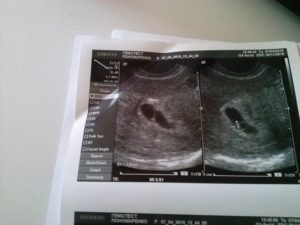

При обследовании может быть назначено УЗИ на 6 неделе беременности. На таком сроке УЗИ позволяет определить наличие плода в матке, то есть, исключить внематочную беременность. Можно увидеть, сколько плодных мешочков начали свое развитие в матке, то есть, выявит многоплодную беременность.

На таком сроке плод мало напоминает ребенка, эмбрион выглядит, как зернышко фасоли, да и его размер напоминает зернышко. Но зато при проведении УЗИ можно будет увидеть сердцебиение плода.

На 6 неделе необходимо сделать первое узи – вы сможете услышать стук сердца малыша.